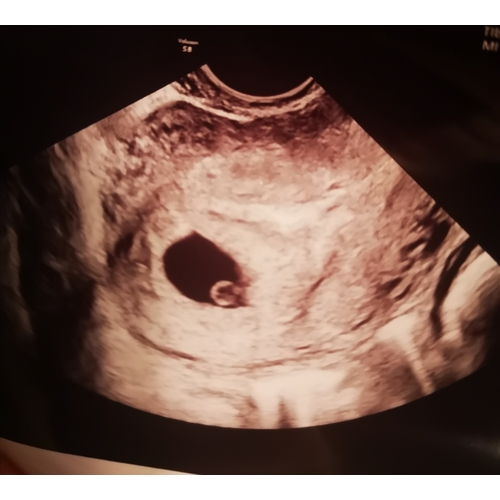

Heb je misschien een foto van de echo? Ik heb met naar mijn schatting een echo gehad met 5.5 weken maar er was bij mij alleen een vruchzak te zien en nog geen vruchtje , ik maak me daar best zorgen om! Zijn er meerdere die dit hebben gehad?

Reactie op srnvdle

Heb je misschien een foto van de echo? Ik heb met naar mijn schatting een e ...

Hi! Zie foto! Hoe zag die er bij jou uit mss?

Reactie op Karo88

Bij mij zag je wel die ronde zwarte vlek alleen niet het vruchtje, de verloskundige zei dat het nog te vroeg kon zijn maar ben zo bang dat er straks niks zit of iets